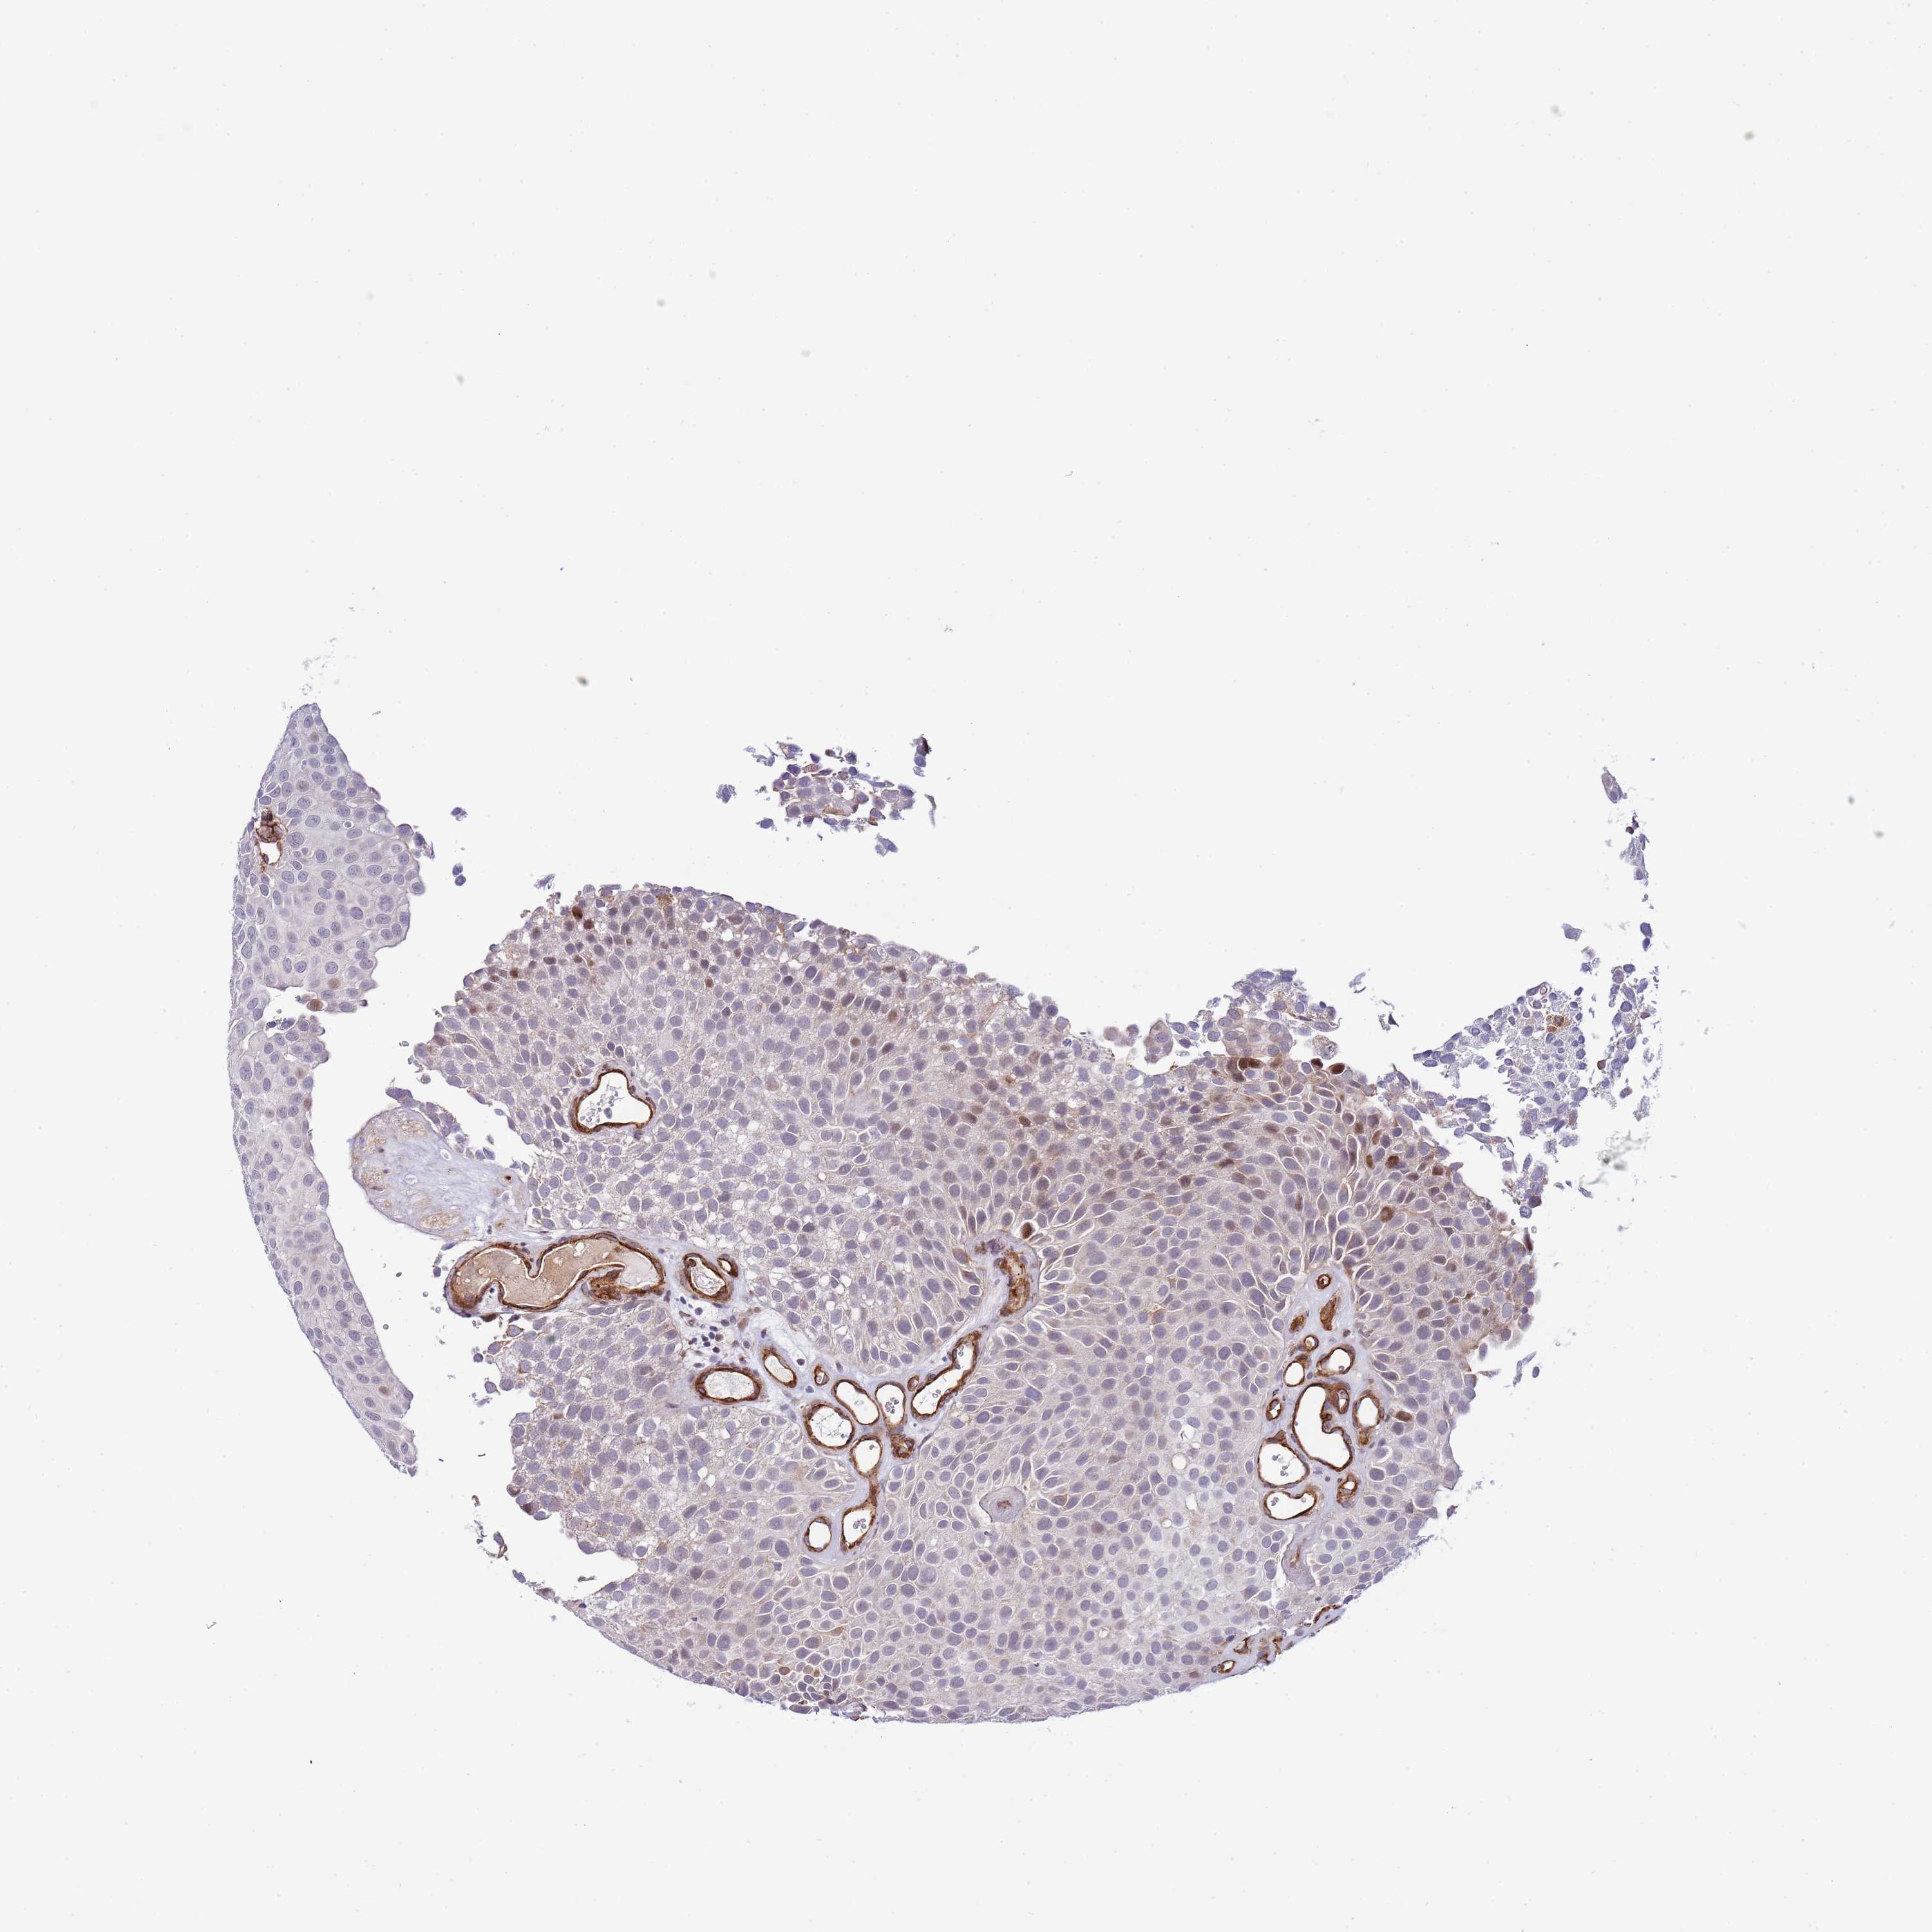

UROTHELIAL CANCER - Protein expressioni

A mouse-over function shows sample information and annotation data. Click on an image to view it in a full screen mode. Samples can be filtered based on level of antibody staining by selecting one or several of the following categories: high, medium, low and not detected. The assay and annotation is described here.

Note that samples used for immunohistochemistry by the Human Protein Atlas do not correspond to samples in the TCGA dataset.

Antibody stainingi

Antibody staining in the annotated cell types in the current human tissue is reported as not detected, low, medium, or high, based on conventional immunohistochemistry profiling in selected tissues. This score is based on the combination of the staining intensity and fraction of stained cells.

Each image is clickable and will lead to virtual microscopy that enables deeper exploration of all samples and also displays staining intensity scores, fraction scores and subcellular localization as well as patient and tissue information for each sample.

Antibody HPA019062

Antibody HPA043230

Staining

High

Medium

Low

Not detected

Intensity

Strong

Moderate

Weak

Negative

Quantity

>75%

75%-25%

<25%

None

Location

Nuclear

Cytoplasmic/membranous

Cytoplasmic/membranous,nuclear

Urothelial carcinoma, High grade

Urothelial carcinoma, Low grade